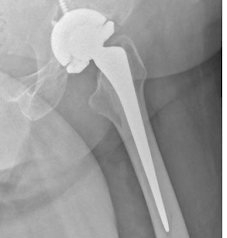

Radiografias mostrando solturas da prótese de quadril.